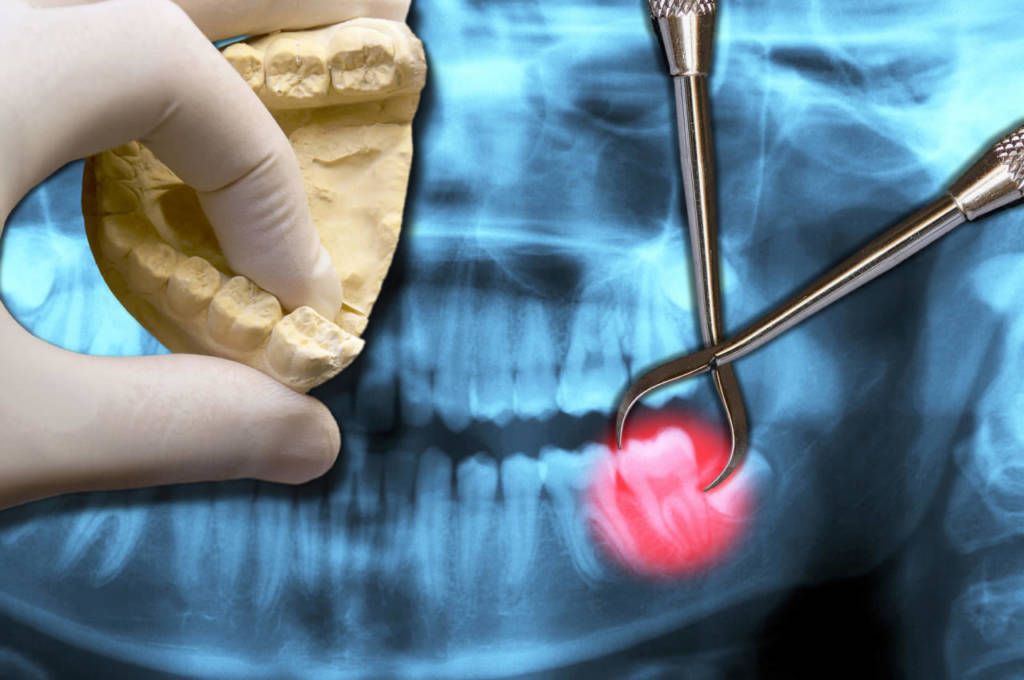

Le indagini radiografiche rivestono un ruolo fondamentale in ogni disciplina odontoiatrica. Infatti, grazie alle radiografie è possibile studiare l’anamnesi del paziente, identificare con precisione l’anatomia del cavo orale e l’eventuale presenza di patologie per una diagnosi precoce e una migliore pianificazione del trattamento.

La nostra apparecchiatura radiografica Cone Beam 9000 3D, installata presso il centro dentale di Loano, vanta la più alta risoluzione delle immagini e la più bassa radiazione (fino a 20 volte inferiore rispetto alle apparecchiature tradizionali) della sua categoria: viene utilizzata sia per panoramiche dentali, sia per indagini Tac occorrenti per una o entrambe le arcate.

Grazie a questo macchinario è possibile valutare, oltre all’altezza e alla larghezza, anche la profondità dell’osso. Ecco perchè rappresenta la soluzione diagnostica ideale per il posizionamento di impianti dentali, in quanto permette di valutare la relazione del “futuro impianto” con i vari elementi presenti nel cavo orale, nonché per valutazioni endodontiche, parodontali e ortodontiche perché aiuta il dentista nella pianificazione dell’intervento, nella scelta del tipo di impianto e nell’individuare possibili conflitti con le strutture anatomiche della bocca.